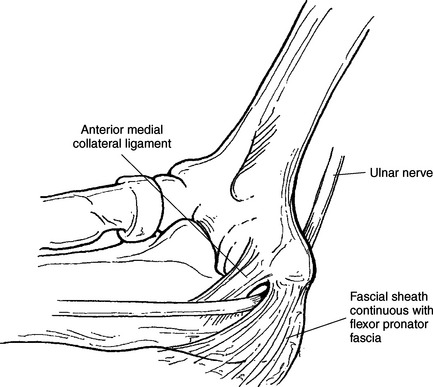

The stability of the elbow joint primarily depends on the collateral ligaments that are woven into the lateral portions of the joint capsule. The ulnar collateral ligament (medial collateral ligament) consists of three components: an anterior band, a posterior band, and a transverse band (ligament of Cooper) (Figures 9.79 through 9.82). The anterior band, which is the strongest, extends from the medial epicondyle of the humerus to the medial aspect of the coronoid process. The posterior band originates along with the anterior band from the medial epicondyle of the humerus and inserts on the medial aspect of the olecranon process, forming a triangular plate. The weaker transverse band stretches between the medial surfaces of the coronoid and olecranon processes to unite the anterior and posterior bands. Reinforcing the lateral side is the triangular radial collateral ligament (lateral collateral ligament). The radial collateral ligament originates from the lateral epicondyle of the humerus, adjacent to and beneath the common extensor tendons, and spreads distally to insert on the annular ligament and the anterior and posterior margins of the radial notch of the ulna (Figures 9.81 and 9.83). The annular ligament forms a fibrous ring that encircles the radial head, with a narrow portion that tightens around the radial neck to prevent inferior displacement of the radius (Figures 9.79 and 9.83 through 9.85). The annular ligament is considered a key structure in the proximal radioulnar joint, allowing the head of the radius to rotate freely. Just distal to the annular ligament is the quadrate ligament, a small band of tissue that passes from the radial notch of the ulna to the neck of the radius to provide stability to the joint during supination and pronation.